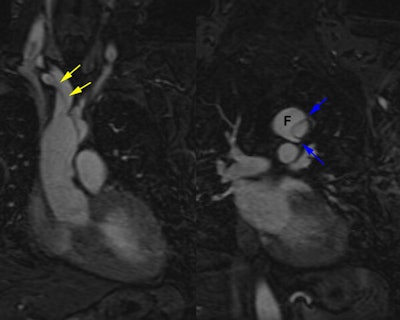

Type A dissection:

The MR exam was performed to better assess possible extension of the dissection into the great vessels. Off axis sagittal images demonstrated the dissection extending into the right inominate artery and right subclavian artery (yellow arrows). The smaller lumen is the true lumen. The "beak sign" described on CT as a feature can also be seen on these MR images. Small "beaks" of contrast in the false lumen (blue arrows) extend around the margins of the true lumen. |